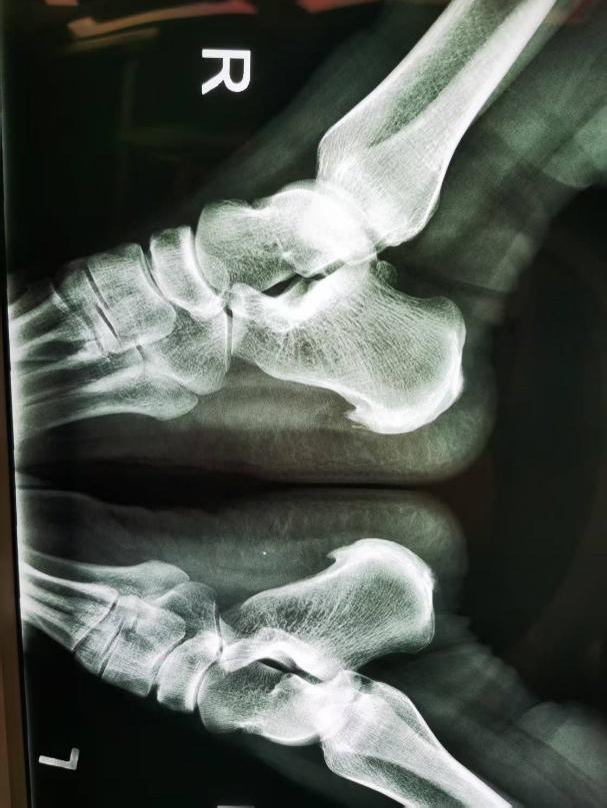

接受手术的是46岁的张大姐,因双足跟部疼痛10月入院,在外口服止痛药物、理疗等治疗效果差,随之来到我院骨一科门诊就诊。骨一科副主任、副主任医师庞涛接诊患者。行双跟骨X光片检查显示双跟骨骨刺,建议患者住院手术治疗。

术前双跟骨骨刺明显